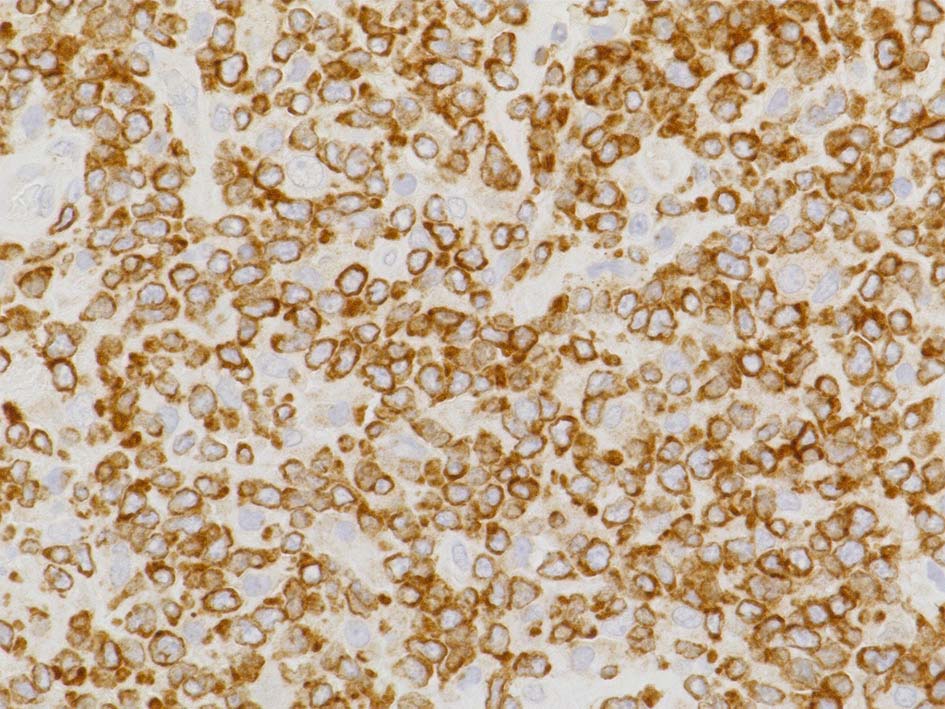

免疫染色

病理診断: Extranodal NK/T-cell lymphoma, nasal type of the testis